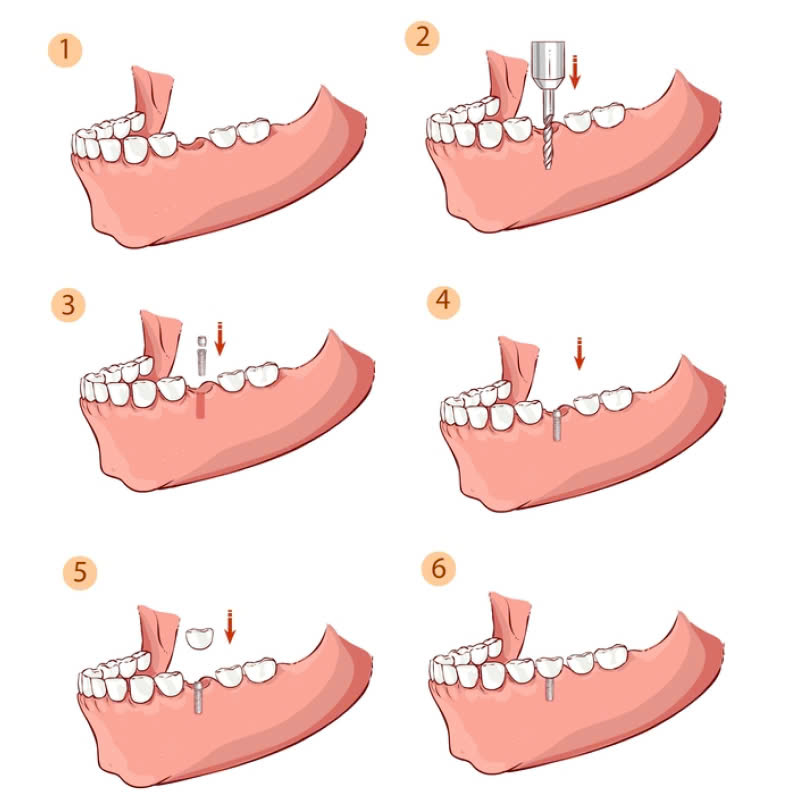

Quy trình trồng răng implant gồm các bước chính sau:

- Bước 1: Khám và tư vấn

Bác sĩ sẽ thăm khám, xác định tình trạng răng miệng, đánh giá sức khỏe tổng quát của khách hàng và tư vấn phương pháp điều trị phù hợp.

- Bước 3: Cấy ghép trụ implant

Bác sĩ sẽ tiến hành cấy ghép trụ implant vào xương hàm, sau đó khâu vết thương.

- Bước 4: Thời gian liền xương

Trồng răng implant cần thời gian để tích hợp vào xương hàm, khoảng 3-6 tháng.

- Bước 5: Lắp mão răng sứ

Sau khi trụ implant liền xương, bác sĩ sẽ tiến hành lắp mão răng sứ lên trụ implant.